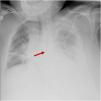

Although echography guidance can increase the success rate of central venous catheter (CVC) placement, it only ensures that the catheter is correctly placed at the level of the vessel entrance. Once the guidewire is inserted there is little we can do to ensure its correct direction on a simple procedure like this one. This is the example of this patient, with left pneumonic empyema in which x-ray confirmation showed CVC migration (Fig. 1). Anecdotally, the only adverse effect reported from this misplacement was acute chest pain on fluids bolus infusion. On chest computed tomography scan, the catheter can be seen going down the left jugular vein and straight inside the brachiocephalic vein (Fig. 2 star) toward the left internal thoracic vein (Fig. 2 arrow).

This incident highlights the importance of routine X-ray visualization of CVC placement, as echography alone cannot completely replace it.